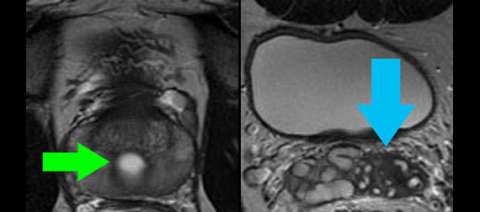

LEFT: Axial cross-section through the lower part of the Muellerian duct remnant cyst (green arrow) shows it lies midline in the peripheral gland. The prostate itself is normal.

RIGHT: Axial cross-section above the level of the prostate shows the seminal vesicles are atrophic on one side only (blue arrow) although the other side appears somewhat disordered, likely related to obstruction from the cyst (not pictured at this level).